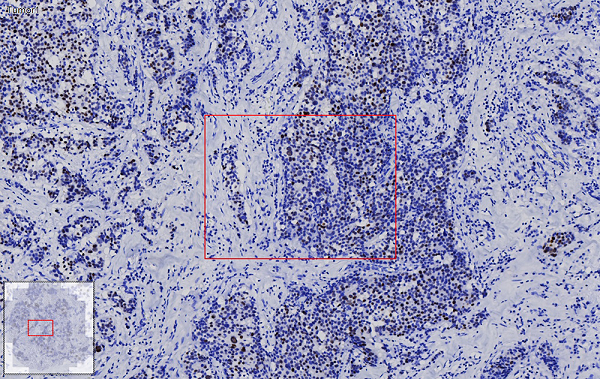

ROI圈选